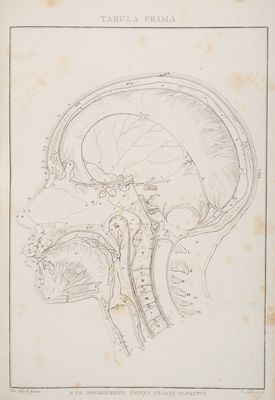

Abbildungen der menschlichen Organe des Geruches / [Von] Samuel Thomas Soemmerring.

- Samuel Thomas von Sömmerring

- 1809

Credit: Abbildungen der menschlichen Organe des Geruches / [Von] Samuel Thomas Soemmerring. Source: Wellcome Collection.